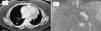

Mujer de 53 años, afecta de dolor abdominal crónico, fue remitida al objetivar en la tomografía axial computarizada (TAC) (fig. 1A) una masa de 6cm en ovario izquierdo, múltiples nódulos pulmonares bilaterales y una masa sólido-quística de 11cm paramediastínica izquierda. Tenía antecedentes de histerectomía por un LU 12 años antes, no era fumadora y estaba asintomática. La función pulmonar, la broncoscopia y la analítica fueron normales. En el PET-TAC no existía captación, y la resonancia magnética (fig. 1B) identificó una masa paramediastínica heterogénea, lobulada y bien definida.

A) TAC torácica que muestra un corte transversal de la masa paramediastínica izquierda y un nódulo en el segmento 6 derecho que se biopsió. B) Resonancia magnética torácica que muestra masa paramediastínica izquierda de 11cm heterogénea, con componente sólido y quístico, lobulada y de contornos bien definidos.